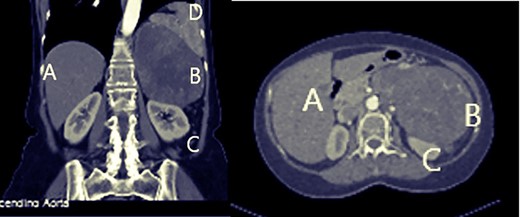

Abdominal ultrasound showed a 16 cm mass in the left adrenal position, abutting the spleen, left kidney and pancreas. A whole body computed tomography (CT) scan showed: a (14.5 × 9.8 cm) well circum heterogeneously enhancing soft tissue mass, pressing the spleen and pancreatic body and tail, the mass seemed to be in the left adrenal vicinity did not extend to the midline. Both kidneys and urinary systems showed no abnormalities (Fig. 1). The right lobe of the liver showed two nodular lesions, 7 and 5 mm, suggesting hemangiomas. No adenopathy in retroperitoneal space was noticed. A positron emission tomography (PET) scan was obtained, and it showed the same primary huge mass uptaking fluorodeoxyglucose, confirming the carcinogenic origin with no distant metastases at that time. Colonoscopy revealed a mass effect at splenic flexure, with no other abnormalities till 20 cm of the ileum.

Abdominal computed tomography: A: liver, B: mass, C: left kidney.